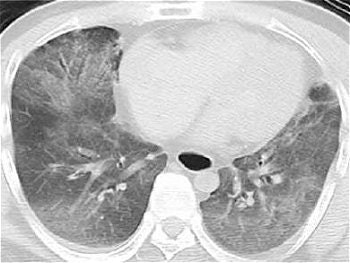

Their patient was a 46-year-old male smoker with no history of cardiac disease. He was found in his home, dead from cardiopulmonary arrest. A whole-body postmortem CT exam was done 30 minutes after death and showed diffuse ground-glass attenuation in both lungs, suggestive of pulmonary edema due to cardiac pump failure, but there was no sign of ischemic myocardium, wrote lead author Dr. Seiji Shiotani, from the department of radiology. Shiotani's co-authors are from the departments of pathology, cardiology, internal medicine, and emergency medicine.

![]() |

| Postmortem CT of the chest shows diffuse ground-glass attenuation in both the right left lower lobes. |